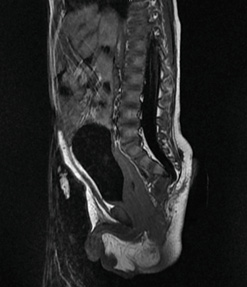

В возрасте 4 лет проведено МРТ органов малого таза. По данным исследования выявлены признаки объемного образования пресакрального пространства, явно компрометирующее ампулу прямой кишки в средней ее трети, с наличием осложненных и неосложненных кист, а также признаками копчикового свищевого хода, гипоплазией копчика (рис. 6).

Рисунок 6.

Объемное образование ректоректальной области и пресакральной области с наличием осложненных и неосложненных кист (МРТ органов малого таза)

Figure 6.

Bulky formation of the rectorectal region and the presarcic region, with the presence of complicated and uncomplicated cysts (MRI of the pelvic organs)